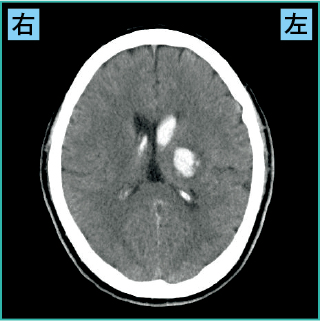

2)視床出血の画像の見方

図3は視床出血の画像です。

図3 視床出血(CT)

責任血管は後大脳動脈から分岐する視床穿通動脈と視床膝状体動脈です。

視床は感覚神経が通る部分であり、反対側の感覚障害や運動神経が通る内包も近くにあるため、反対側の運動麻痺が出現することがあります。また、視床は意識にもかかわっているため、意識障害や、眼球が内側下方に向く(鼻先凝視)の共同偏視を認めることがあります。

図3の症例では、左の視床と内包が障害され、意識障害、右半身の運動・感覚障害が出現していました。

なお、視床出血は脳室内に出血が及ぶ脳室穿破(せんぱ)が多い脳出血です(図3も側脳室が白くなっており、出血が脳室内に及んでいるのがわかります)。脳室穿破を合併すると、意識障害が重度になってしまうことがあります。急性水頭症になると手術が必要になる場合もあり、予後不良になってしまいます。